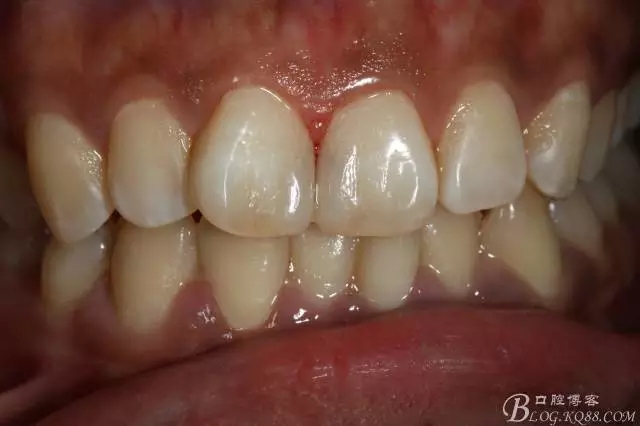

3mz250充填完成即刻照

(2014年9月復(fù)查時(shí)樹(shù)脂邊緣明顯做了一次拋光處理,當(dāng)時(shí)就建議做貼面未果??上?這次沒(méi)有留得照片)

2016.1復(fù)查情況很不好,再次建議做瓷貼面并告知各自?xún)?yōu)缺點(diǎn)。這回患者同意并選擇鑄瓷貼面。